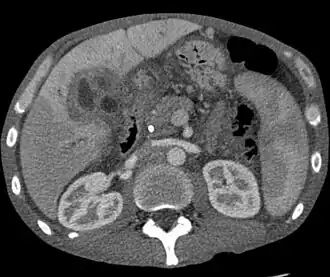

| Tomografia de um colangiocarcinoma. | |

A principal causa de cancro no fígado é a cirrose causada por hepatite B, hepatite C ou consumo de álcool.[4] Entre outras possíveis causas estão a aflatoxina, doença hepática gordurosa não alcoólica e parasitas do fígado.[3] Os tipos mais comuns são o hepatocarcinoma (80% dos casos) e o colangiocarcinoma.[3] Os tipos menos comuns incluem a neoplasia cística mucinosa do pâncreas e a neoplasia intraductal papilar do ducto biliar.[3] O diagnóstico pode ser apoiado por análises ao sangue e imagiologia médica e confirmado por biópsia.[1]